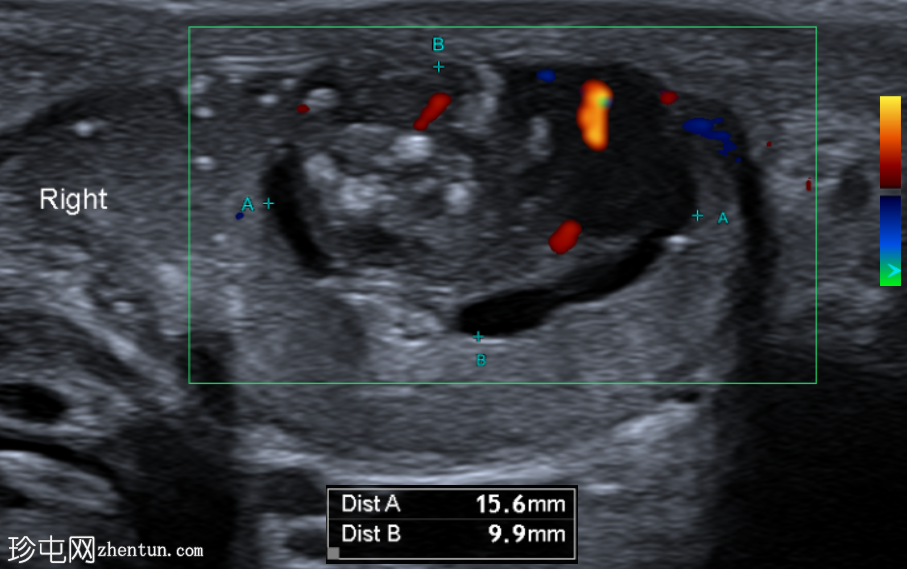

纵切面

右侧睾丸内可见一异质性肿块,大小约10 x 14 x 15 mm,包含实性和囊性成分。肿块内可见多发小钙化灶。彩色多普勒超声检查显示肿块内血流信号较少。